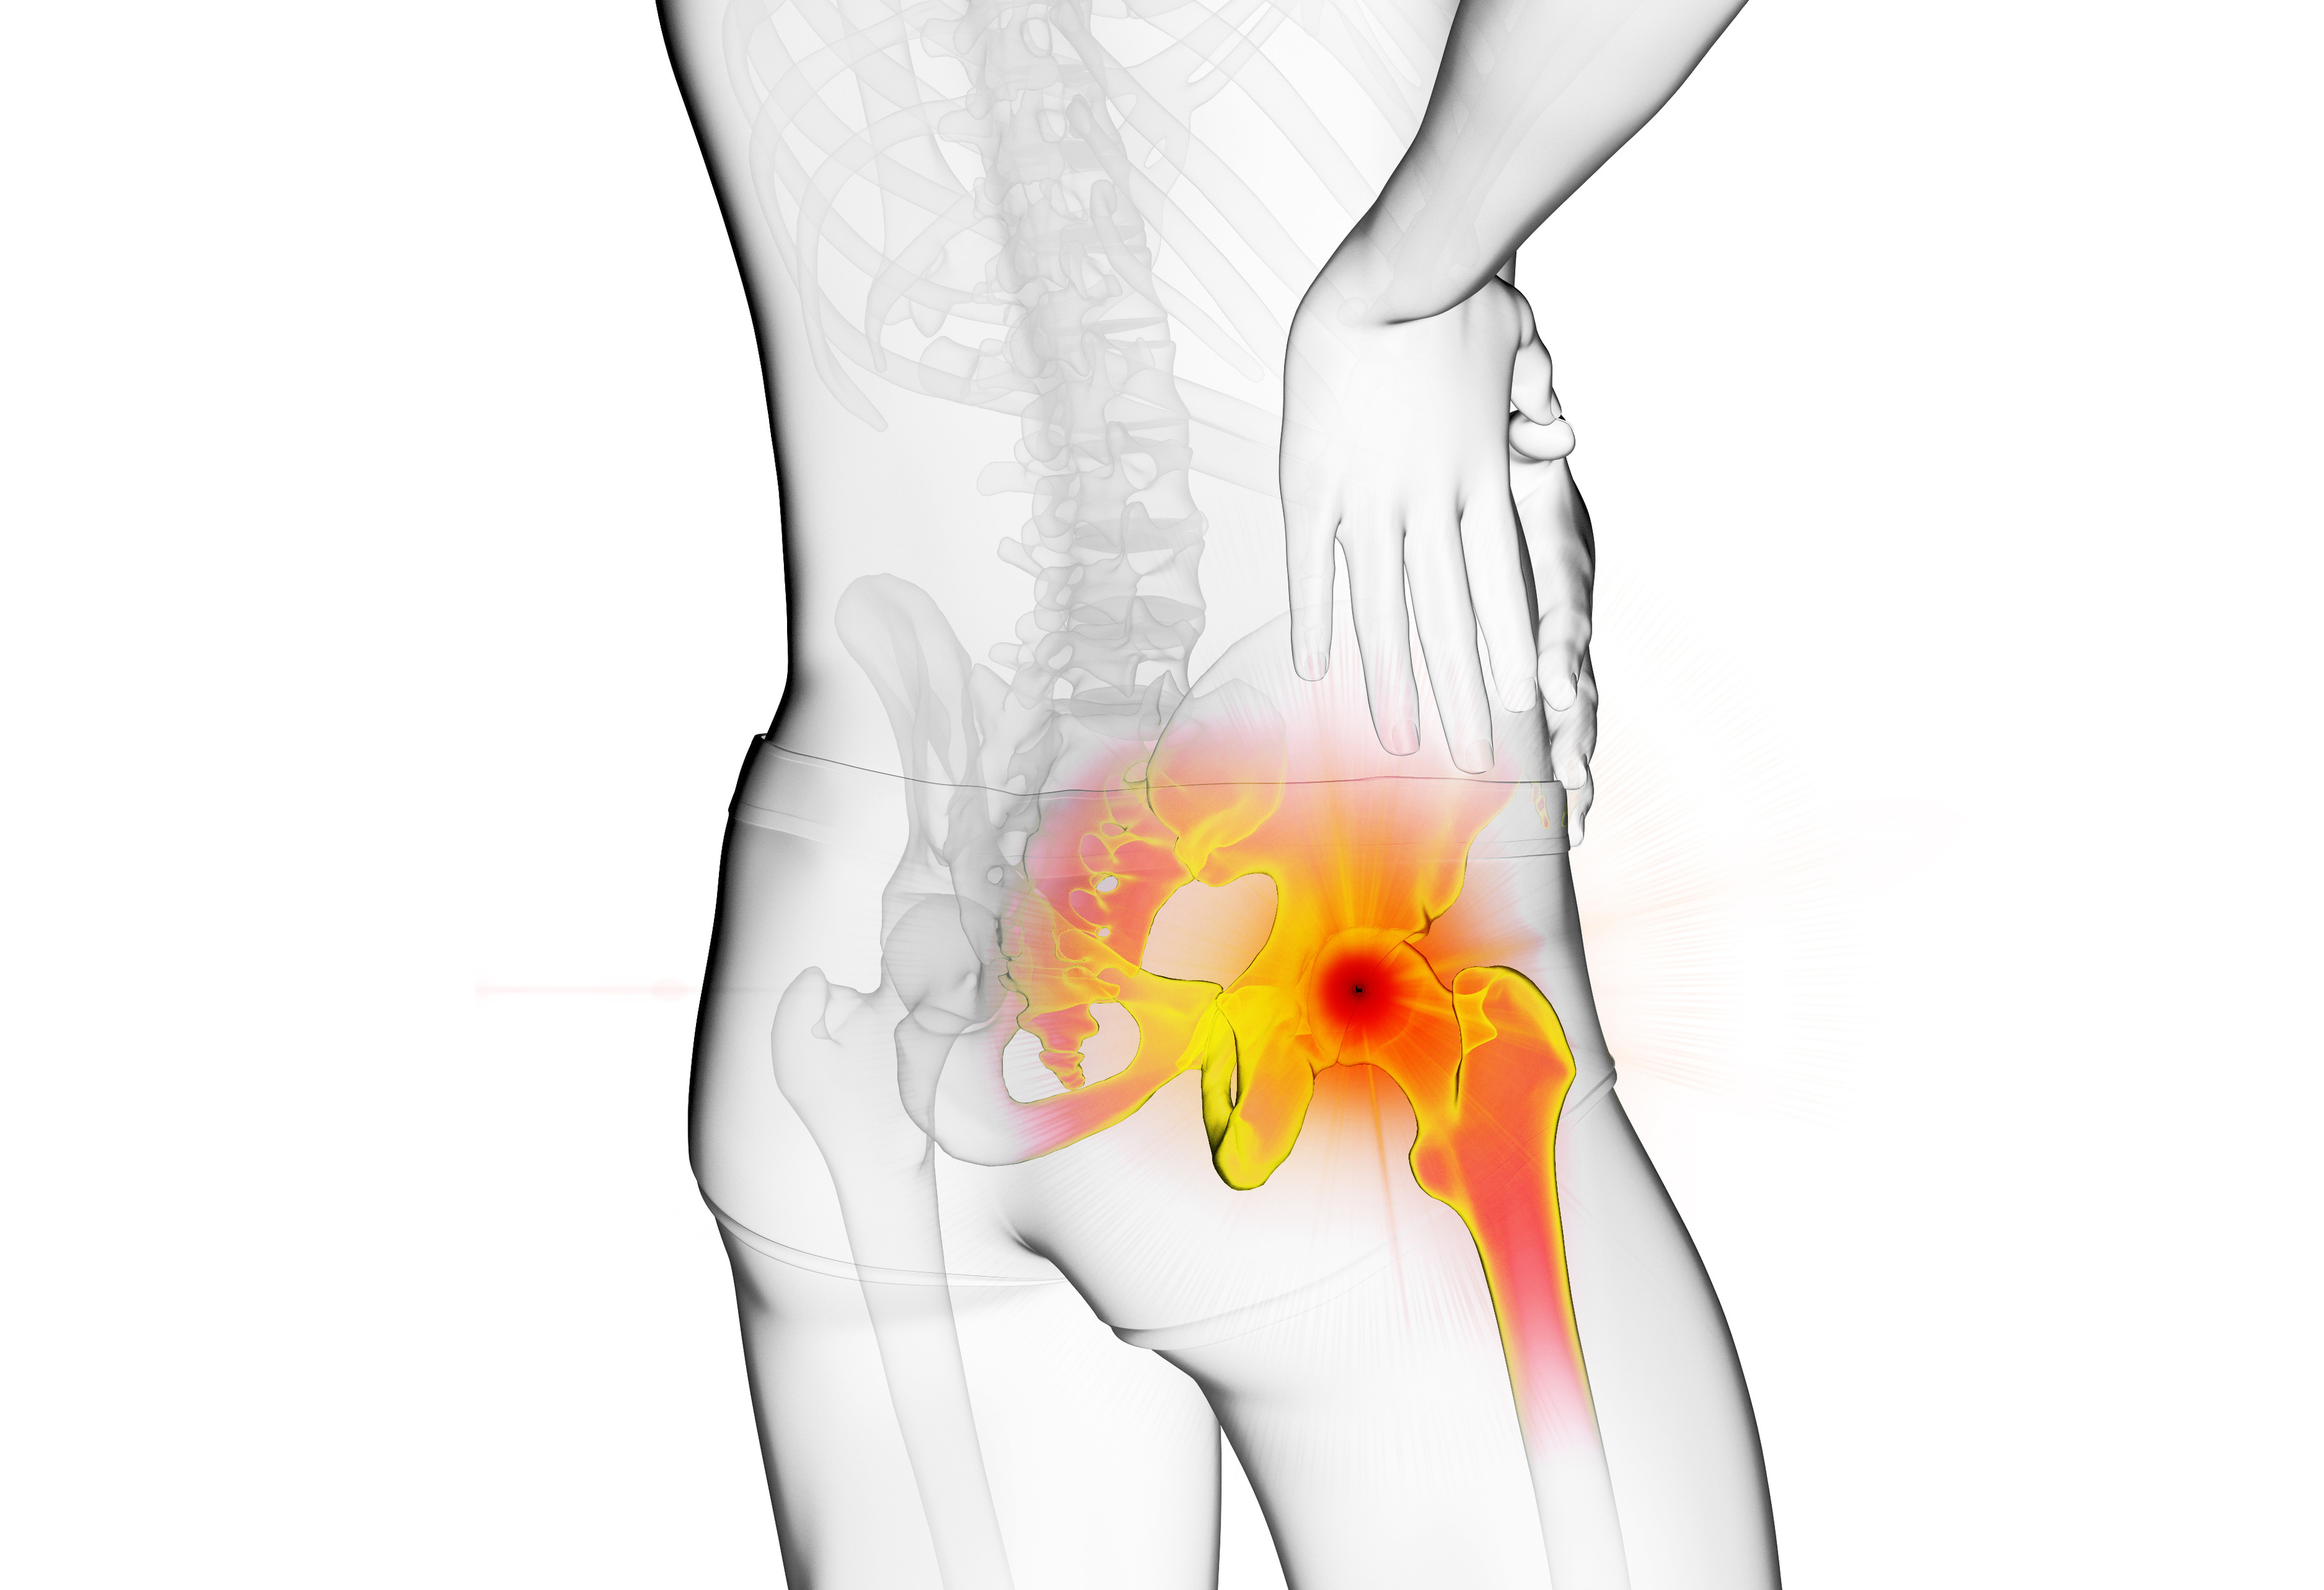

대퇴골두의 혈액순환 장애로 뼈 조직이 괴사되고 괴사된 뼈에 압력이 지속적으로 가해져 괴사부 위가 골절되면서 통증이 나타나는 질환입니다.

· 사타구니가 뻐근하고 보행시 엉덩이 부위가 쑤심과 통증

· 엉덩이, 허벅지, 골반 등 통증 발생

· 양반다리와 같이 다리를 벌린 자세가 어려움

· 장시간 보행시 고관절 전체의 통증 발생